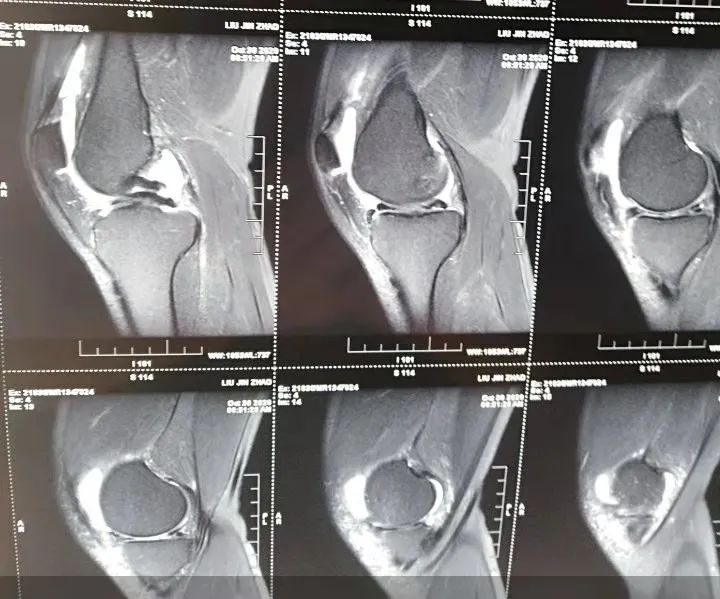

当然,不是所有出现上述症状的患者都是半月板损伤,也可能是别的疾病或损伤,这需要专科医生进行鉴别,比如骨关节炎、髌股综合征、膝关节游离体、骨性关节炎、髌骨软化症、韧带损伤等等。当我们怀疑是半月板损伤时,则需要行磁共振检查明确诊断,MRI可以清晰的显示半月板有无变性、破裂、积液及韧带损伤,是检查膝关节主要方法,对半月板损伤的诊断准确率达96%;正常半月板低信号、滑囊高信号、韧带低信号。磁共振是一种断层扫描,半月板损伤在磁共振检查下分III度:O度为正常半月板,显示为低信号;I度损伤是不与半月板关节面接触局灶性的球状高信号;II度损伤是有线性的高信号,延伸到半月板的关节囊缘,但未达到半月板的关节面缘;III度损伤是半月板后角见到线性高信号,到达半月板的关节面下面。

半月板撕裂在MRI检查中的直接征象:

III级信号,半月板形态异常改变,半月板缺失或移位。